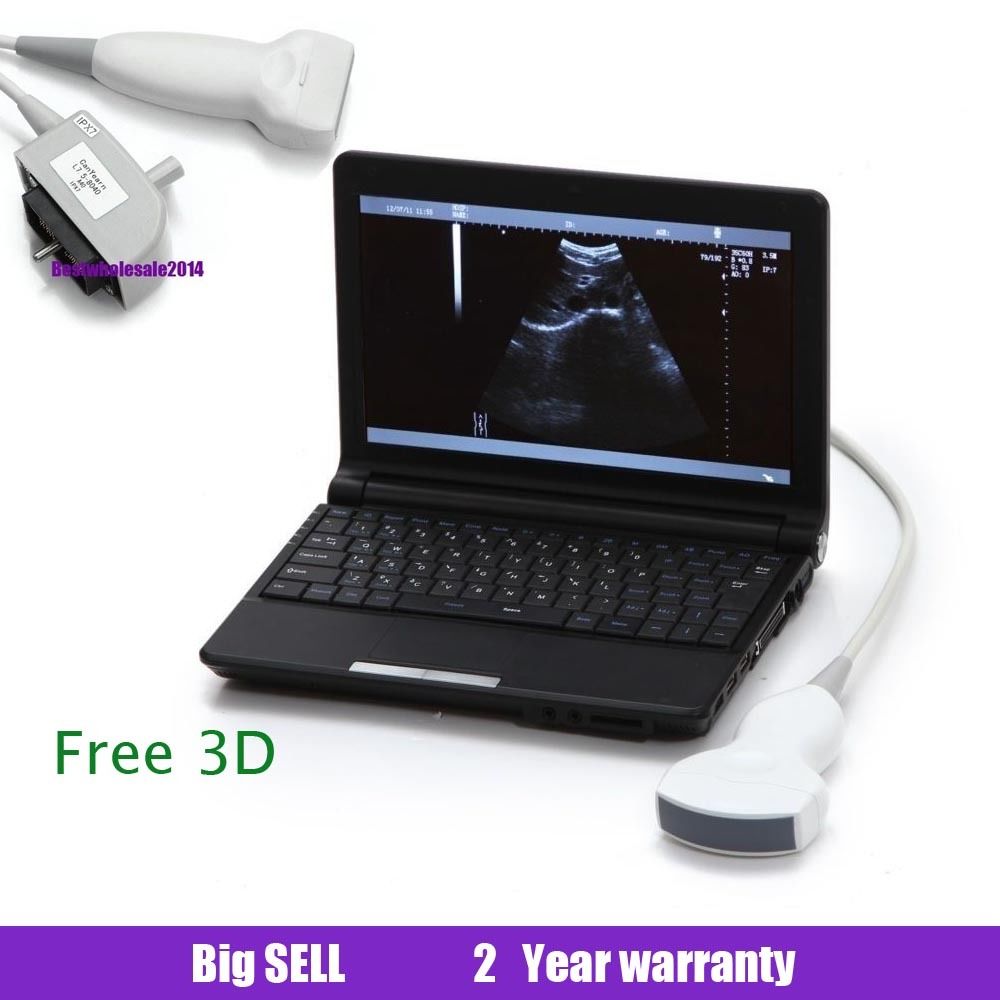

Laptop Ultrasound Machine Portable Medical Scanner with Transvaginal Probe USA 6945040100362

Sale price$ 1,798.00

Regular price$ 1,918.00